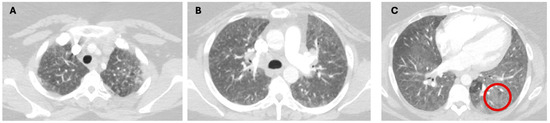

1.1. The Diagnosis and Evaluation of Patients with ILD in the ICU

- Charokopos, A.; Moua, T.; Ryu, J.H.; Smischney, N.J. Acute exacerbation of interstitial lung disease in the intensive care unit. World J. Crit. Care Med. 2022, 11, 22–32. [Google Scholar] [CrossRef]

- Suzuki, A.; Kondoh, Y.; Brown, K.K.; Johkoh, T.; Kataoka, K.; Fukuoka, J.; Kimura, T.; Matsuda, T.; Yokoyama, T.; Fukihara, J.; et al. Acute exacerbations of fibrotic interstitial lung diseases. Respirology 2020, 25, 525–534. [Google Scholar] [CrossRef]

- Alhamad, E.H.; Cal, J.G.; Alrajhi, N.N.; AlBoukai, A.A. Acute exacerbation in interstitial lung disease. Ann. Thorac. Med. 2021, 16, 178–187. [Google Scholar] [CrossRef]